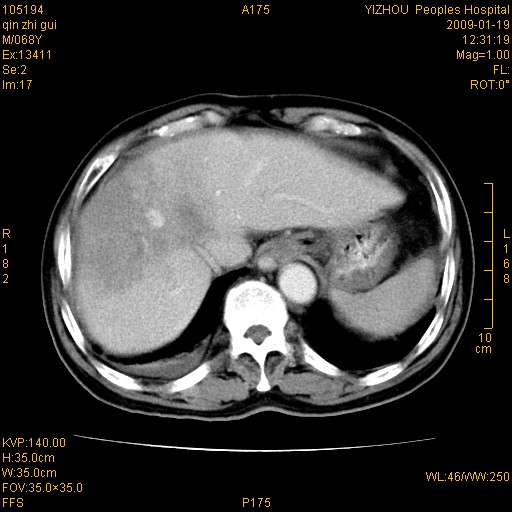

以下是引用随光逐影在2009-1-21 16:11:00的发言:[br]1)考虑肝右叶肝癌并肝静脉及门静脉瘤栓形成。2)肝硬化,少量腹水。3)胆囊炎。4)右侧少量胸腔积液。

病灶外缘凹凸不平,平扫低密度,增强动脉期有强化,门脉早显,静脉期及延期呈延迟强化,结合病史考虑右肝前叶巨块型肝癌可能性大,强化表现不除外胆管细胞癌